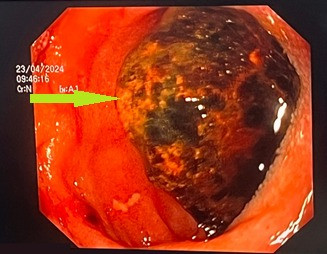

Thông qua hình ảnh chụp cắt lớp vi tính ổ bụng và nội soi tiêu hóa, các bác sĩ chẩn đoán bệnh nhân bị tắc tá tràng do sỏi mật (Hội chứng BOUVERET) kích thước rất lớn 3x5cm rò từ túi mật vào trong lòng tá tràng.

| Hình ảnh sỏi trên phim chụp - Ảnh BVCC |